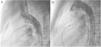

Both patients with history of previous PDA closure were successfully treated. The first was a seven year-old child who had a coil implanted at age three. The procedure was technically difficult, requiring a guidewire capture using a snare catheter to go through the residual PDA (Figure 11), and an Amplatzer duct occluder II 3x4 mm device was implanted successfully. The second patient was a 19 month-old child with PDA and pulmonary hypertension after an unsuccessful surgical ligation. In this case, sizing with a Tyshak balloon was required before implanting an Amplatzer duct occluder II 3x4 mm device (Figure 12).

MethodsAll consecutive pediatric patients referred to our center for percutaneous PDA closure from January 2006 until September 2018 were included in this study. Medical record data was collected and reviewed retrospectively. Informed written consent was obtained from the parents or legal guardians. Indications for closure were presence of cardiac murmur, left-sided volume overload detected by non-invasive cardiac imaging, or signs of heart failure. All procedures were performed under general anesthesia. Arterial access was obtained in all patients. An intravenous bolus injection of 100 IU/kg heparin was administered at the start of the procedure. Our endocarditis prophylaxis protocol consisted of cephazolin 25-30 mg/kg every eight hours for 24 hours, and no anti-aggregation was advocated. In every patient, an aortogram was performed in the lateral projection to define the morphology and size of the duct. According to these results, feasibility for percutaneous closure was determined and, when deemed feasible, appropriate devices were selected. At our department, the Nit-Occlud® occlusion device (pfm, Cologne, Germany) has been available since 2006, with the Amplatzer™ duct occluder being implemented in 2011. As standard of care, all devices were preferably deployed anterogradely. A post-implantation aortogram was obtained to check for residual shunts or any anomaly in the device position. All patients were assessed six hours after the procedure for hemodynamic instability and unpalpable distal arterial pulses. The following day, before discharge, the location of the device was noted on a chest radiograph and a transthoracic echocardiography was performed to exclude residual leakage or other complications. Clinical and echocardiographic follow-up assessments were performed at one, three, six and twelve months after the procedure, and annually thereafter.